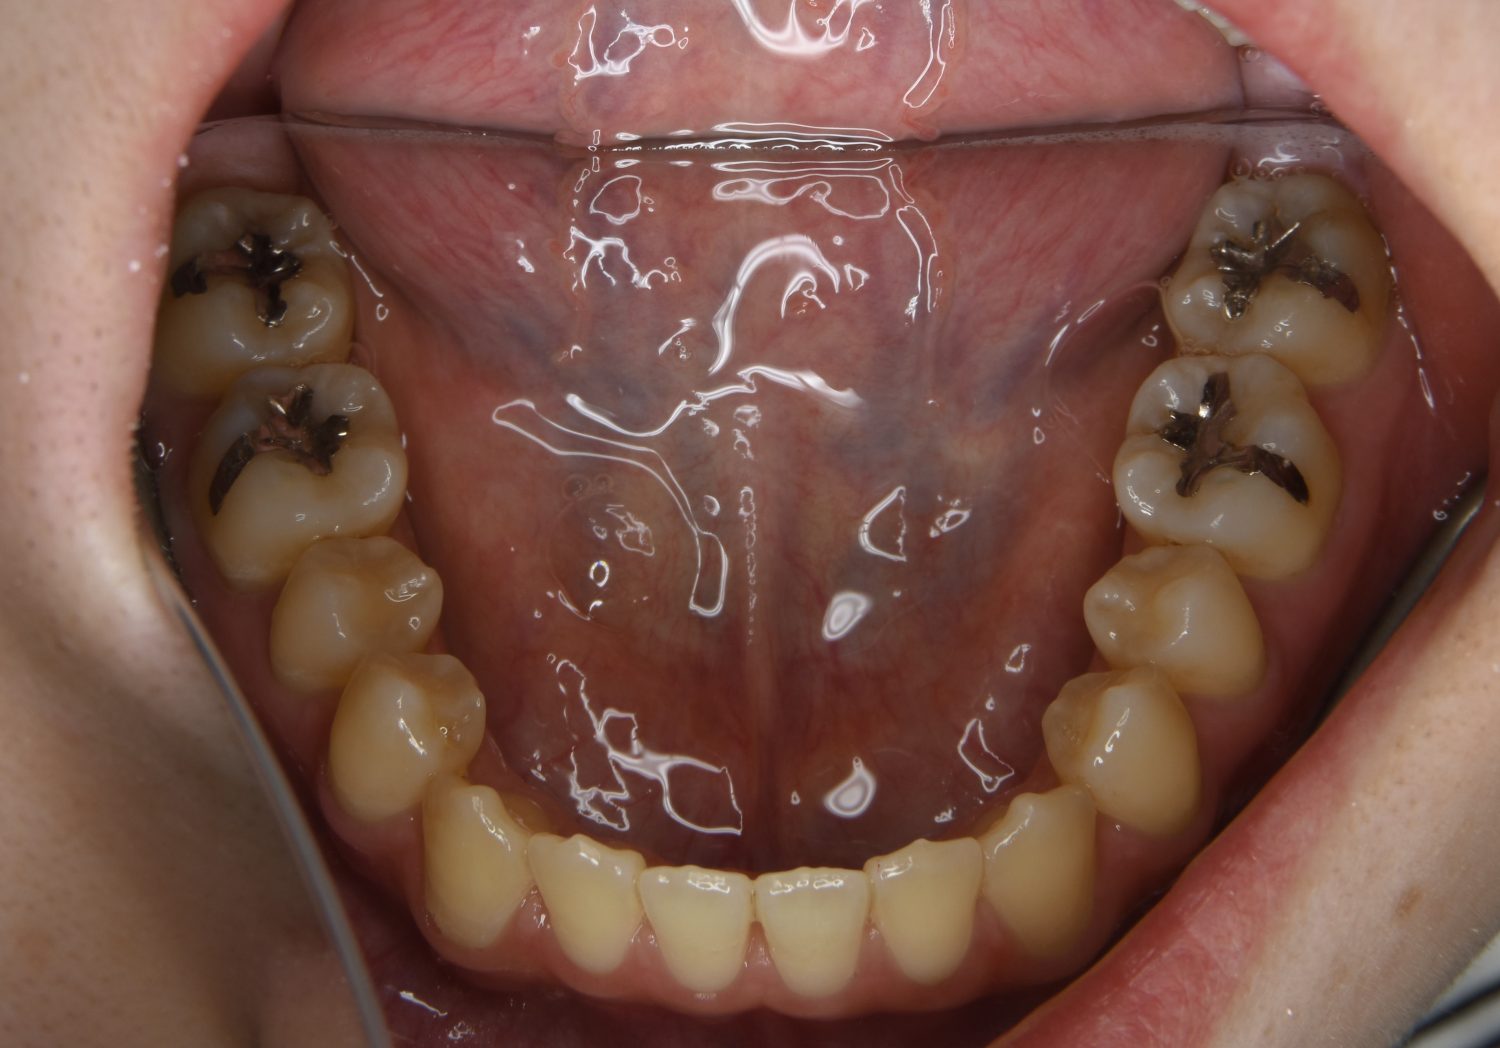

前歯部開咬の症例紹介②

Before

主訴

前歯で物が噛めない

治療内容

上下ラビアルブラケット(唇側装置)に矯正用アンカースクリューを併用し非抜歯で治療を行いました。

治療費

1,000,000 円(税込)

治療期間

26ヶ月

通院回数

27回

想定されたリスク

※歯根吸収、歯肉退縮、歯髄壊死、顎関節症状

上下の前歯が開いており前歯では全く噛めていない状態でした。臼歯の圧下を行うことで機能面のみでなく審美面も改善しました。